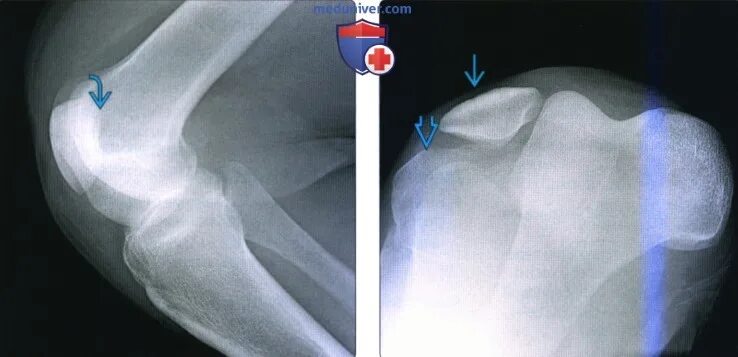

Рентген тазобедренный в двух проекциях